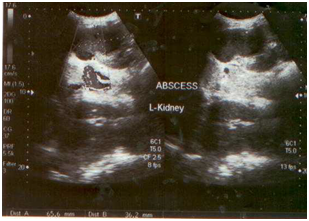

A 30-years old female was admitted to the National Medical Center with the history of persisting fever, headache, weakness, abdominal pain and loss of appetite since last 3 months. A week before arrival to the hospital, she was taking anti tuberculosis treatment (ATT), as prescribed by a local doctor without any actual diagnosis. The consultant after examining patient sent request for blood and urine culture, CBC, liver function tests, urea, creatinine, electrolytes, chest x-ray, ultrasound whole abdomen to the clinical laboratory and radiology department of the hospital respectively. Intravenous fluid infusion and panadol (to manage pain) were given initially to the patient until the investigation results revealed. The blood picture showed 7.9 g/dl (Hb), 424,000 mm3 (PLT) and 7,100 mm3 (WBC) respectively. The renal profile showed urea 10mg/dl and creatinine 0.5mg/dl while liver function tests were found to be within normal ranges. Chest x-ray showed no active lesion excluding pulmonary tuberculosis. The whole abdomen ultrasound showed normal liver, spleen, pancreas, gall bladder, urinary bladder, whereas the right kidney which was of normal size, shape and place. Figure 1A Echogenicity of renal cortex was seen as normal. Corticomedullary distinction was seen intact. But the left kidney was found enlarged (11.9 x 5.5) with perinephric abscess. There was well defined hypoechoic lesion of 6.5 x 3.6 cm noted in upper pole of left kidney extending outside the kidney and filled with thick level echoes inside. Doppler showed no significant flow (Figures 1B & 1C).

Figure 1C Perinephric abscess in left kidney.

On the basis of these clinical findings, the ultrasound guided aspiration was planned and performed under aseptic measures and approximately 50 cc of thick pus aspirated from left perinephric abscess. The pus specimen was sent to microbiology laboratory for culture and sensitivity, AFB smear and AFB culture. The gram stain of the exudate showed few gram negative rods with numerous pus cells. The AFB smear was negative. The non-lactose fermenting gram negative bacilli were isolated from culture that was further processed for identification and antibiotic sensitivity testing. The GNBs were identified as Salmonella typhi on conventional biochemical reactions. The isolate was further confirmed by performing serotyping (remel). The isolate was resistant to ampicillin (10µg, oxoid), chloramphenicol (30µg, oxoid), nalidixic acid (30µg, oxoid) and co-trimoxazole (1.25/23.75µg, oxoid) but interestingly intermediate sensitivity was show to ciprofloxacin (MIC = 0.12µg/ml, oxoid). Ceftriaxone (30µg, oxoid), cefoperazone-sulbactam (105µg, oxoid) were found to be sensitive. No organism was reported from urine culture and blood culture. Widal test was performed from the stored serum sample. The test was found positive with the titer of 1:320 against Salmonella typhi flagellar (H) and somatic (O) antigens. The patient was given intravenous treatment with cefoperazone-sulbactam (1g) twice a day. The symptoms subsided and the patient was discharged on third day of hospitalization with the advice of continuing treatment for 2 more days. The patient showed no symptoms on her follow-up visits to the hospital. Later the AFB culture report was also negative.